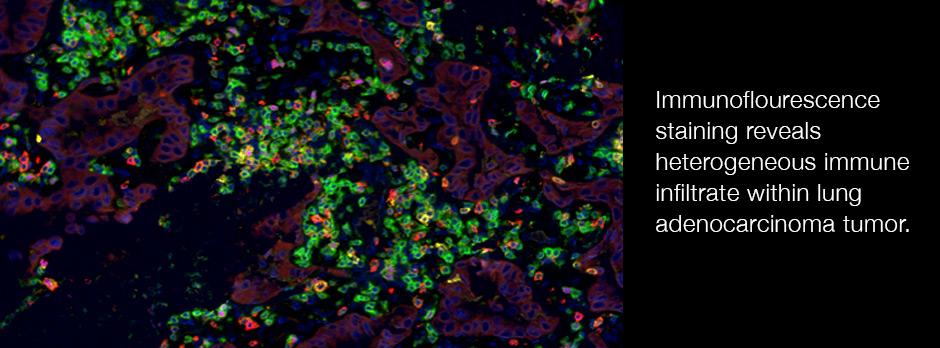

We are leveraging of our expertise in conditional gene targeting, cutting edge multimodal single-cell sequencing, and our great relationship with clinical collaborators to pursue projects related to both basic immunology (B and T cell development) and clinically relevant questions in infection, autoimmunity and cancer.